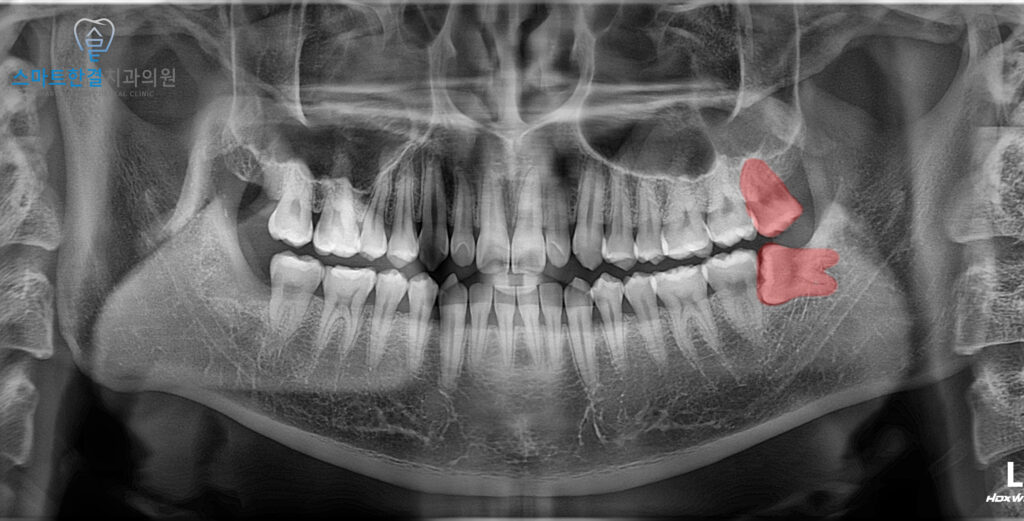

위 사진에서 위, 아래

2개의 화서동사랑니를 깨끗하게

발치한 모습 보이시나요?

위쪽 사랑니는

비교적 바르게 자라 있었지만,

저작 기능에는 큰 도움이

되지 않는 상태였어요.

특히 맞물리는 치아가 없는 경우,

사용되지 않으면서 점차

아래로 과도하게 내려오거나

주변 잇몸과 뼈에 자극을 주어

통증이나 염증을 유발할 수 있기 때문에

이런 점을 고려하여 본원에서는 함께

발치하시는 것을 권해드렸어요. ^^

아래쪽 사랑니는 머리 일부만 노출된 채

옆으로 누운 방향으로 자라고 있어,

잇몸을 부분적으로 절개한 뒤

정밀하게 제거하고

깨끗하게 마무리해 드렸어요.